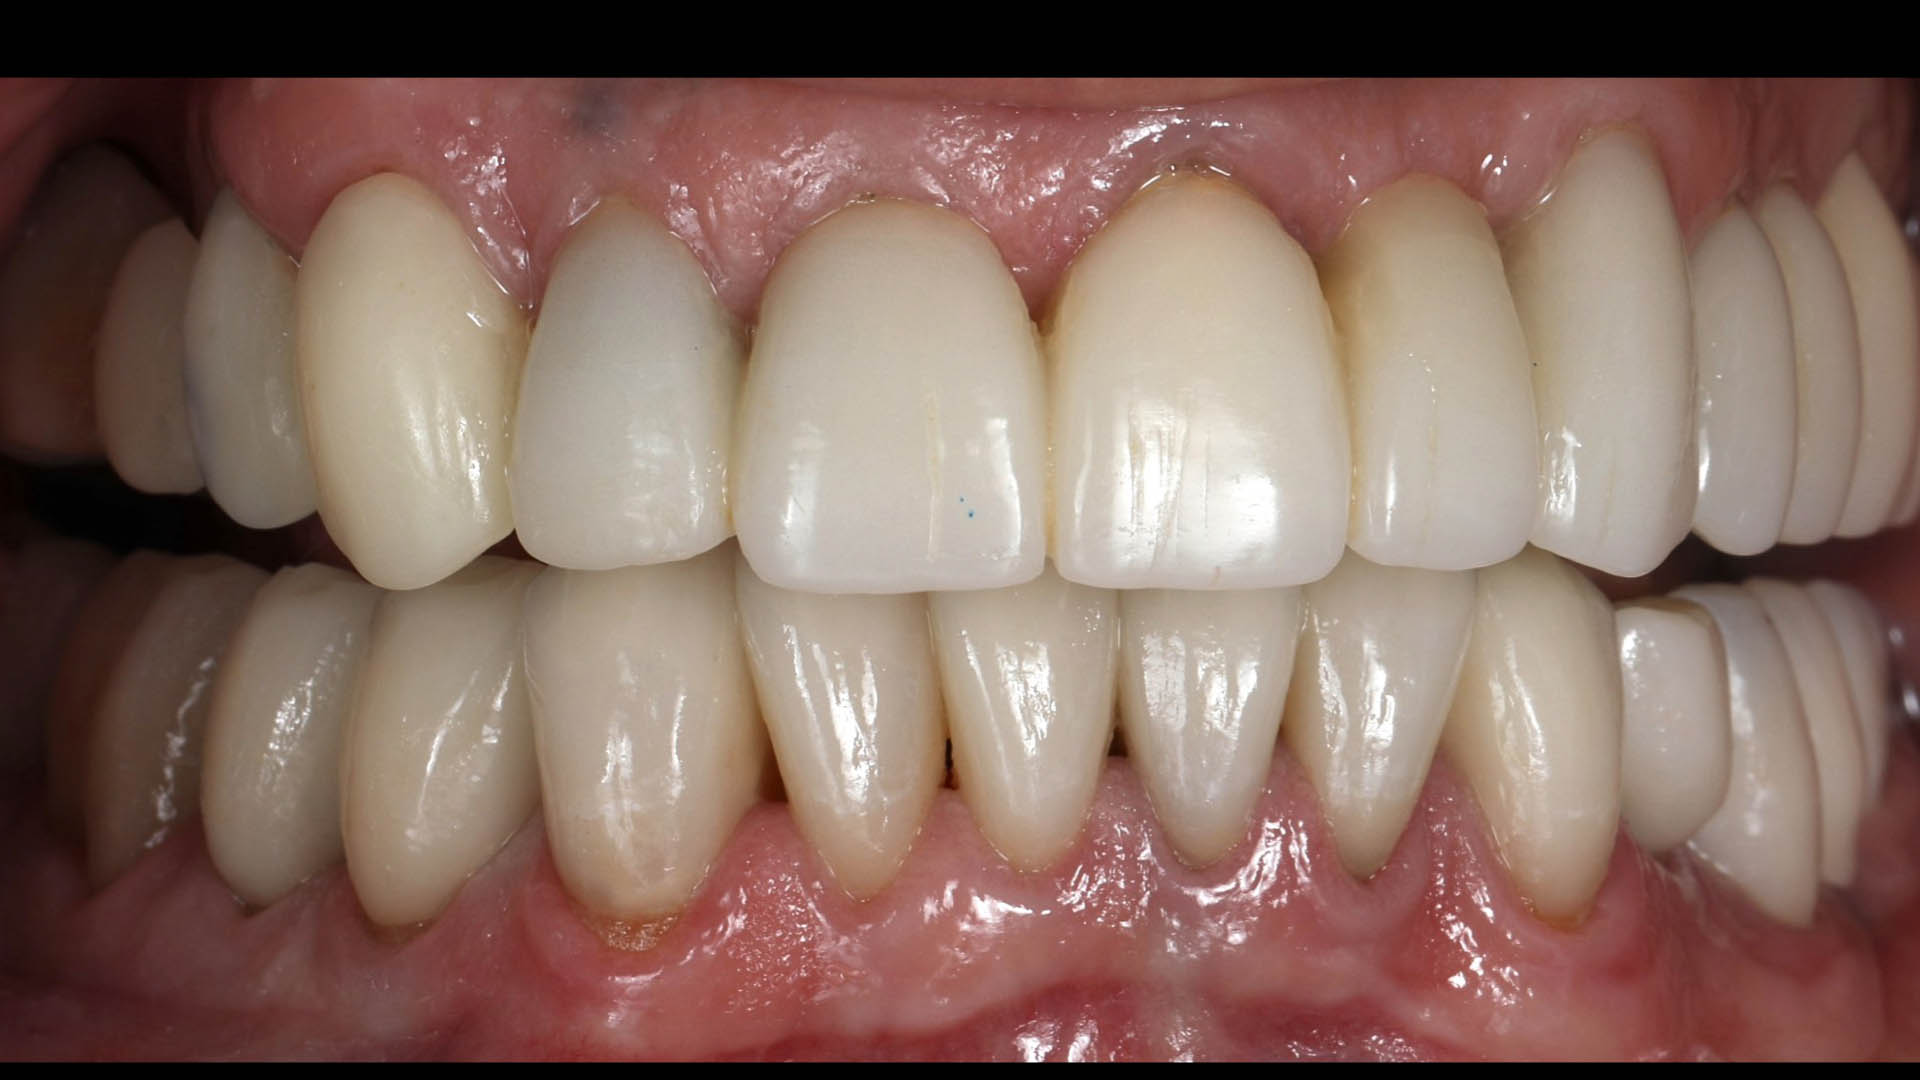

Take a glimpse into the magic of Coral Gables Dentistry through our before and after pictures. See firsthand the incredible smile makeover transformations that have brought confidence and joy to our patients.